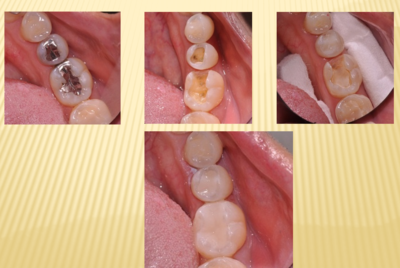

それで、現在主に保険治療で使われているのが、コンポジットレジンという合成樹脂とコンポジットレジンにセラミックが混じったハイブリッドセラミックと言われるものです。保険治療の詰め物で主に使われているのは、コンポジットレジンです。相当昔から前歯の治療には使われていましたが色調に問題があったり、歯の神経(歯髄)に為害作用がありましたが、改良に改良を重ねられて、現在では生体親和性もあり、見た目にも強度の面でも良くなってきて、奥歯の詰め物にも使われるようになってきました。しかしこのコンポジットレジンには大きな欠点があります。重合収縮と言われるものです。コンポジットレジンは柔らかい状態で虫歯を取ってきれいにした状態のところに接着剤を塗布して詰めてゆき、そこにある波長の光を当てて固まらせます。固まる時に重合収縮という現象が起きます。重合収縮は接着剤が弱いと詰めたコンポジットレジンと歯牙との間にわずかな隙間(ギャップ)を作ったり、接着剤が相当に強いと歯の方にわずかなひび(クラック)が入ったりします。(図2、図3)大きい詰め物や隣接面(歯と歯が連なっている面)にかかる詰め物の場合は、詰め物と歯牙の面積と体積が大きくなるので重合収縮が大きくなり、2次カリエスの原因になります。そこで、大きい詰め物や隣接面を含む詰め物は、セラミックを使うのです。セラミックそのものは歯とは接着しないので、コンポジットレジン系の接着剤を使うのですが、数十ミクロン(1㎜は1000ミクロン)なので、重合収縮は無視できるのです。(図4)セラミックを使うことによって2次カリエスの原因であるギャップやクラックを防ぐことが出来ます。これまでの長石系のセラミックでは破折することが見られたのですが、2ケイ酸リチウム系のセラミックやジルコニアセラミックを使用することでそのようなトラブルがなりました。

小さな修復物でも、理想的にはセラミックを使うのがいいのですが、小さいものは取扱いに大変困ってしまいます。小さいと出来上がったものを調整研磨しているときに、どこに行ったか分からなくなってしまうこともあります。みと歯科・矯正歯科では、小さい修復物はコンポジットレジンで、大きな修復物や隣接面を含む修復物はセラミックを使った修復物をすすめています。大きな修復物の形態、特に隣接面の形態、隣接面のくっつき具合をコンポジットレジンで適切に作るのは大変難しく、セラミックをコンピュータで設計し削りだす方が正確です。重合収縮は、コンポジットレジンにはどうして避けられない物理的な性質ですから、それに賢く対処していくことが、2次カリエスを防ぎ、一度治療した歯を長くもたせる秘訣だと思います。(図5)